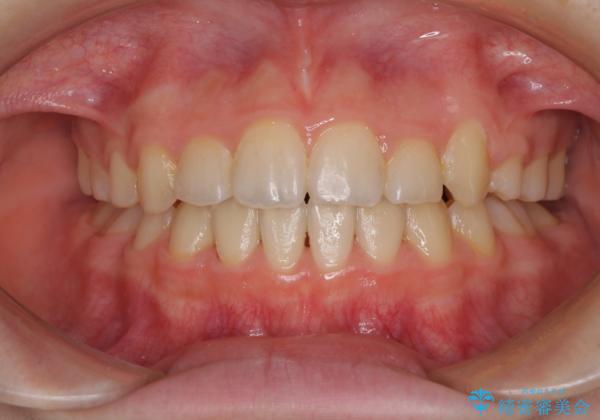

乳歯が残っている 目立たない装置での抜歯矯正

- クリアブラケット

- 2年1ヶ月

下顎の乳歯は永久歯と比べて幅が大きいため、抜歯した場合のスペースが大きく、治療には長期間を要することが一般的です。

今回の患者様は中学生ということもあり、成人の患者様と比べ動きが速く、2年間で治療を終えることができました。